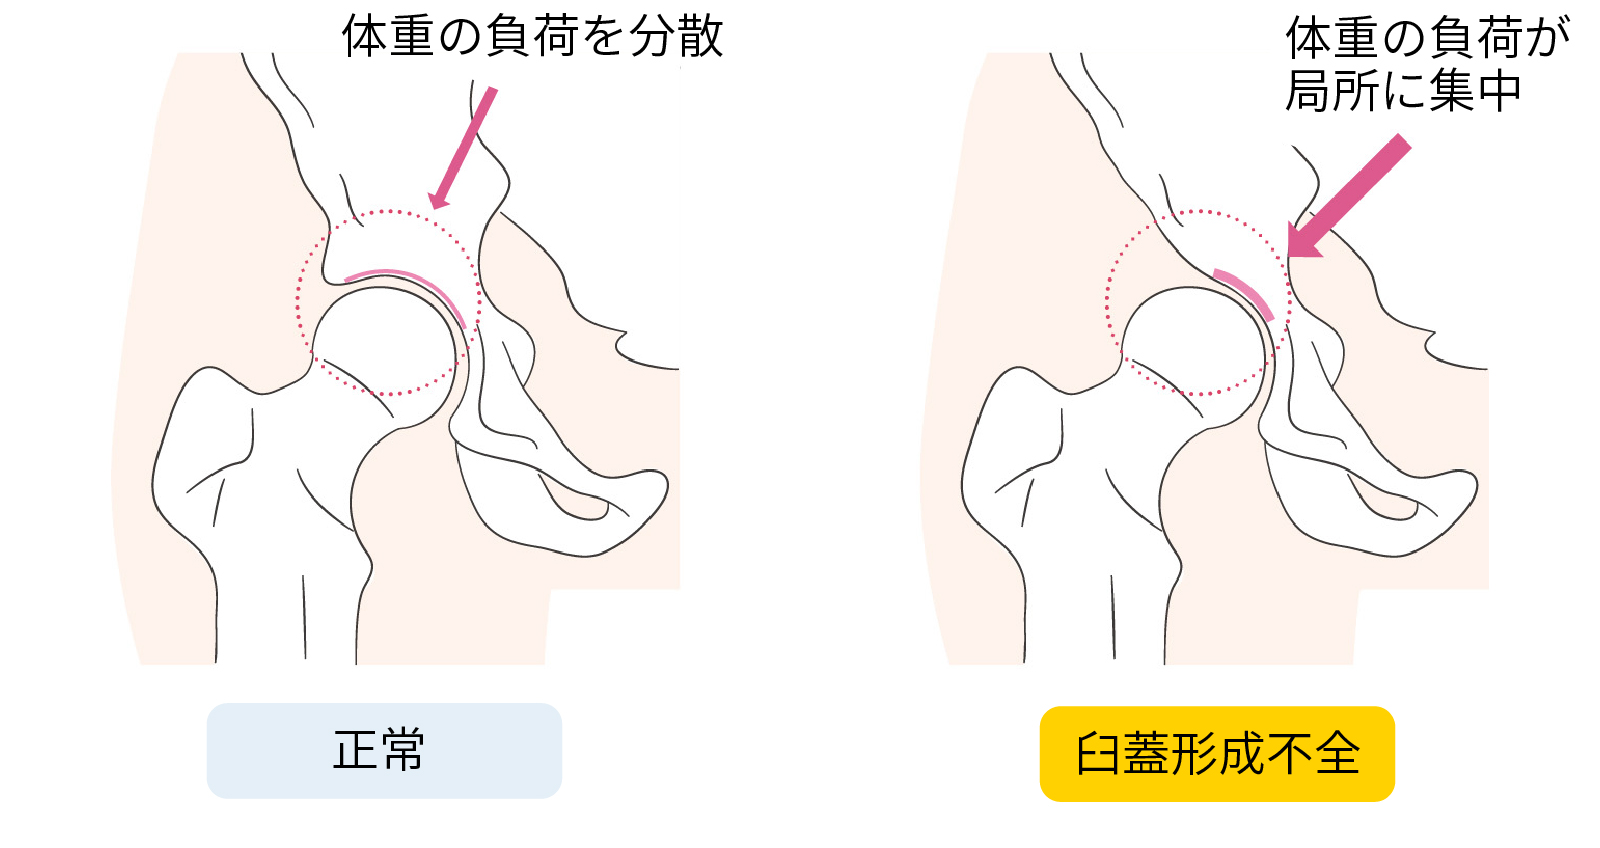

臼蓋形成不全

きゅうがいけいせいふぜん

股関節の受け皿(臼蓋)が浅く、多くの場合、生まれつき関節のかぶりが不十分な状態です。このため股関節に負担がかかりやすく、将来的に変形性股関節症へと進行することがあります。